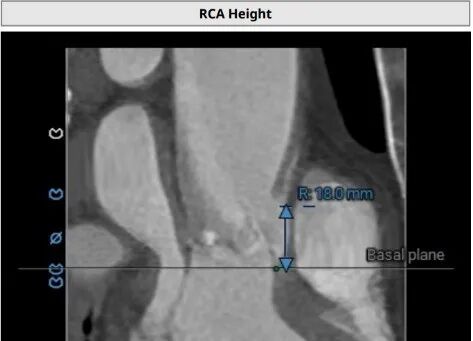

手术风险、难点

患者左冠脉开口高度11.0mm,左冠窦瓣叶长度14.3mm, 瓣叶明显增厚,有轻度钙化。应注意术中有冠脉闭塞风险。患者未见明显心室隔膜部,新发的房室传导阻滞风险较高。